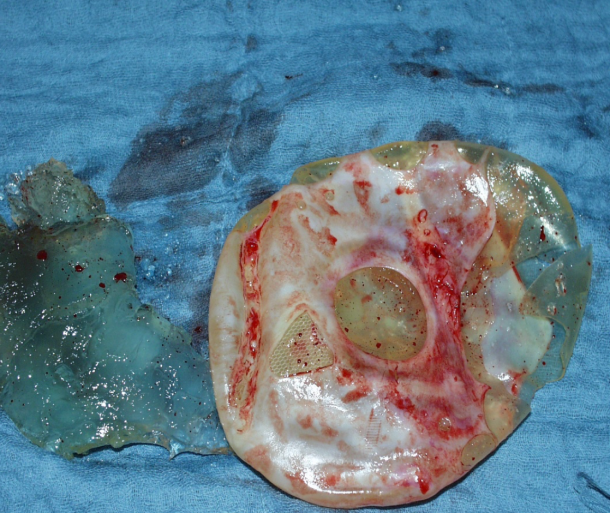

Other possible complications of gluteal implants

explosion gluteal implant

gluteal scars